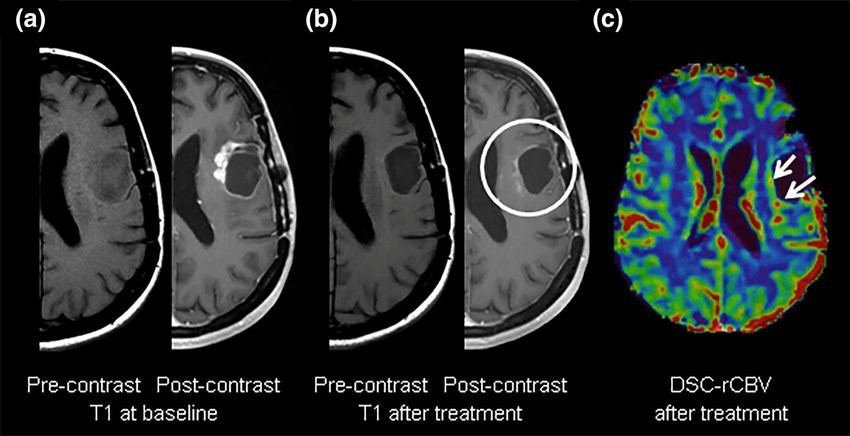

ماژول BioQuant که بر کاهش سیگنال ناشی از حساسیت در توالی های دارای وزن *T2 تکیه دارد که ناشی از افزایش مقادیر کنتراست مبتنی بر

گادولینیوم از بستر مویرگی است، توسعه داده شده است. متداول ترین پارامترهای محاسبه شده در این ماژول rCBV ،rCBF و MTT به عنوان

پرفیوژن MR تقویت شده با کنتراست با حساسیت پویا است که هنوز به اختصار DSC نامیده می شود.

این ماژول همچنین مشخصات بیولوژیکی تومور را برای تشخیص و نظارت بر گلیوما مشخص می کند.